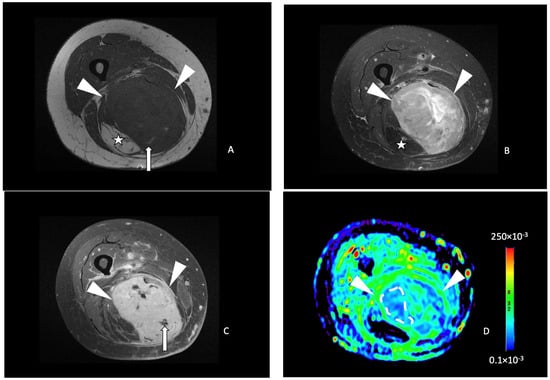

The median ADC value in the STS studied was 134.3 (101.7–167.9) × 10−3 mm2/s. The median tumor-to-muscle ADC ratio was 1.00 (0.77–1.55). There was a significant correlation between the ADC value and the post-treatment tumor necrosis percentage (p = 0.013) with a fair Spearman correlation coefficient (0.47). There was also a statistically significant correlation between the tumor-to-muscle ratio ADC and the post-treatment necrosis percent (p = 0.011) with a 0.48 Spearman correlation coefficient. Among the 20 tumors with less than 50% necrosis after RT, the median ADC value was 120.3 (97.7–161.6) × 10−3 mm2/s (Figure 3), while in tumors with more than 50% necrosis, the mean ADC value was significantly higher: 202.0 (160.9–243.6) × 10−3 mm2/s (p = 0.020) (Figure 4). For tumor-to-muscle ratio ADC, the difference was also significant with median ratios of 0.93 (0.72–1.25) and 1.55 (1.18 to 1.81) for tumors with under and over 50% of histologic necrosis (p = 0.045).

Figure 3.

A 41-year-old male with a spindle cell sarcoma of the left elbow. Axial T1-weighted (A), axial T2-weighted fat-saturated (B) and axial T1-weighted contrast-enhanced (C) MR images showing an ovoid mass (white arrowheads) with a homogeneous hypointense T1 and hyperintense T2 signal with a heterogeneous enhancement with a central necrotic portion (arrow in (C)) in the superficial soft tissue, with close contact with the aponeurosis and the olecranon process. (D) Axial ADC functional map of the same tumor. A free-form ROI (white line) delineates the tumor area with the lowest ADC identified and was positioned within it, yielding a mean ADC of 92 × 10−3 mm2/s (<161 × 10−3 mm2/s). A free-form ROI (green line) of the corresponding size was positioned in the muscle. The tumor necrosis percentage after neoadjuvant therapy was 0%, corresponding to a poor response to treatment.